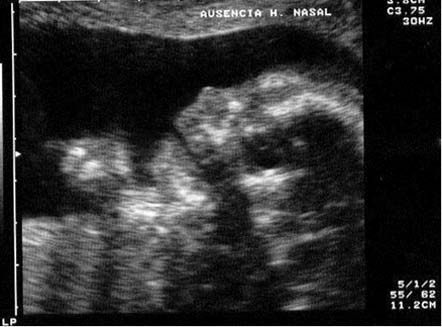

Ausencia de hueso nasal

Este es un marcador de primer orden para el síndrome de Down, más del 60 por ciento de los Down tienen ausencia de hueso nasal.